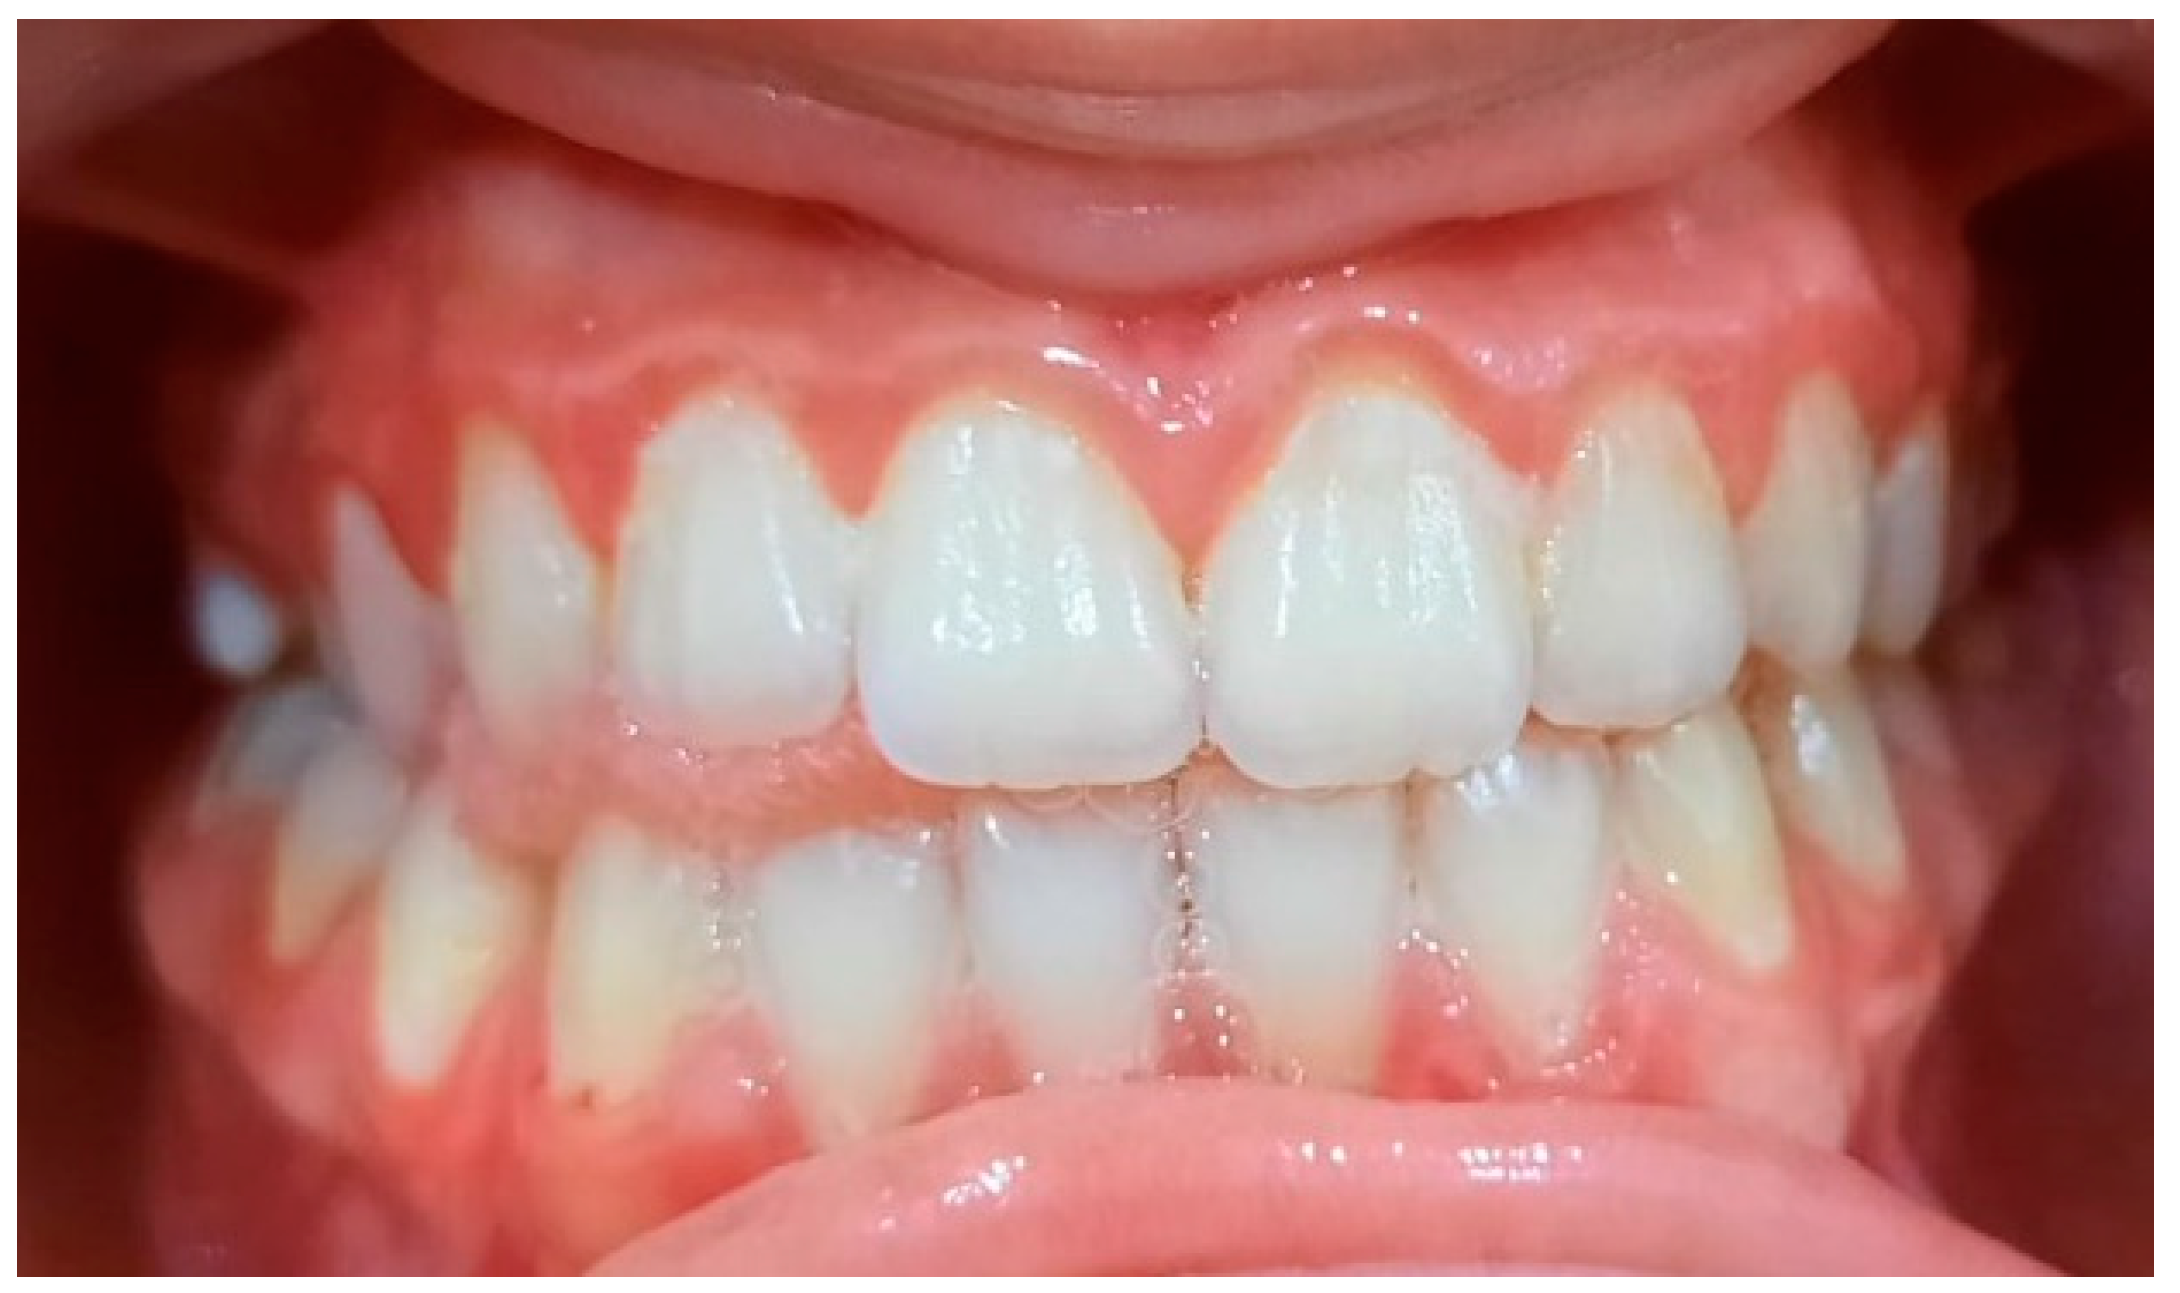

2.2. Clinical Examinations

2.5. Specialist Treatment

3.2. Analysis of Clinical Data